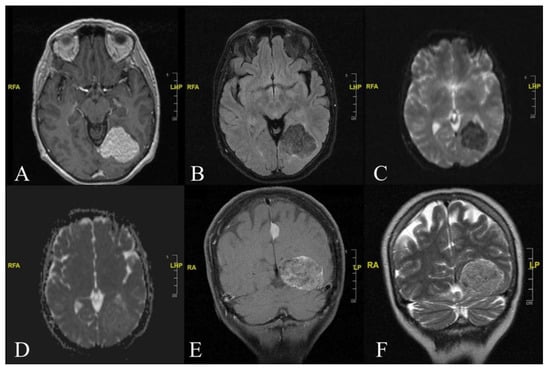

Visual Aura Secondary to Supratentorial Lipomatous Meningioma: A Rare Case Report

2. Case Report